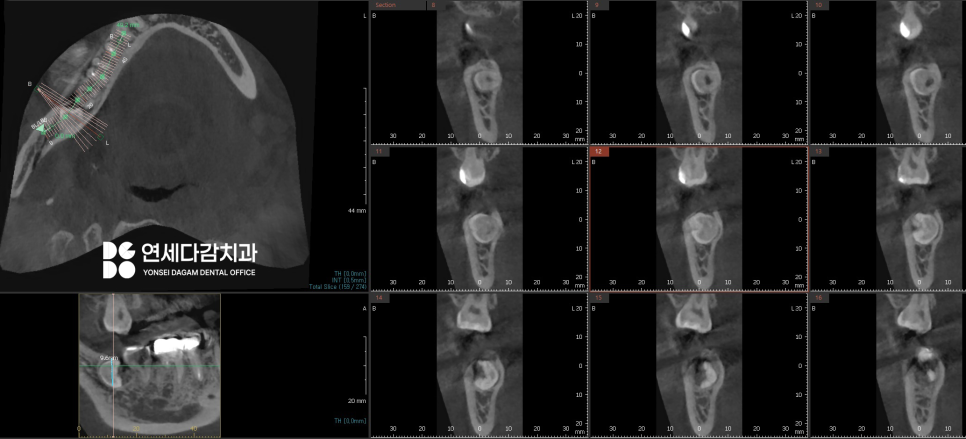

이러한 복잡한 케이스에서는

CT 촬영을 통해 3차원적인

구조 분석을 통해

안전한 발치 전략을

미리 수립하는 것이

필수 과정입니다.

수평으로 매복된 경우,

CT 분석 결과 하치조신경과

근접해 있는 경우가 많습니다.

하치조신경은 아래턱의

감각을 담당하는 주요 구조물이므로,

손상되면 감각이상이 생길 수 있습니다.

마찬가지로 사전 분석을 통해

치료 전략을 세우고,

계획에 따라 분할 발치를

시행하여 치아 조각이

남지 않도록 깔끔하게 치료를 완료합니다.